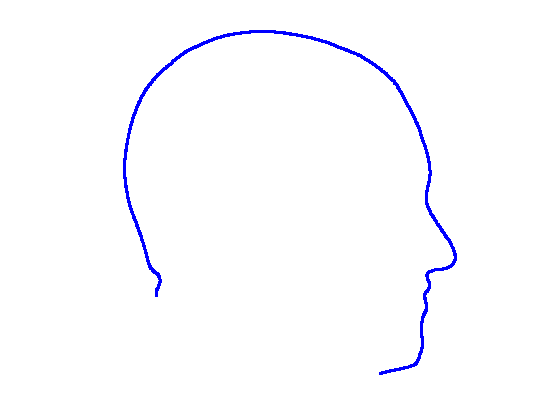

For each of the three segments, we determine the range of gradients on that segment by simple differencing between consecutive points. Each segment is rotated into a 2D frame such that maximum absolute values of positive and negative gradients are equal. Cubic spline contours are fitted to the three profiles and the head profile contour is reconstructed using the three individual cubic splines. Fig. 14 show examples of these.

|